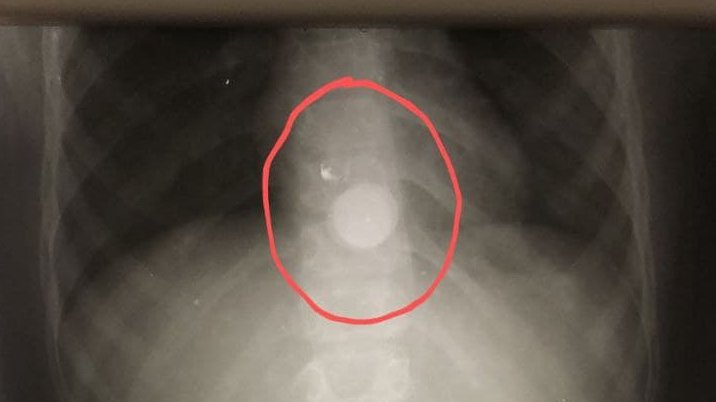

В Подмосковье врачи достали монету из пищевода 8-летней девочки

Ребенок проглотил 1 рубль во время игры

В одну Московскую областную больницу имени профессора Розанова обратились родители 8-летней девочки. Они сообщили врачам, что ребенок нечаянно проглотил рублевую монету. Однако родителям девочка сообщила об этом лишь спустя 12 часов.

Врачи извлекли монету без операции, с помощью специального зажима, сообщает пресс-служба Министерства здравоохранения Московской области.